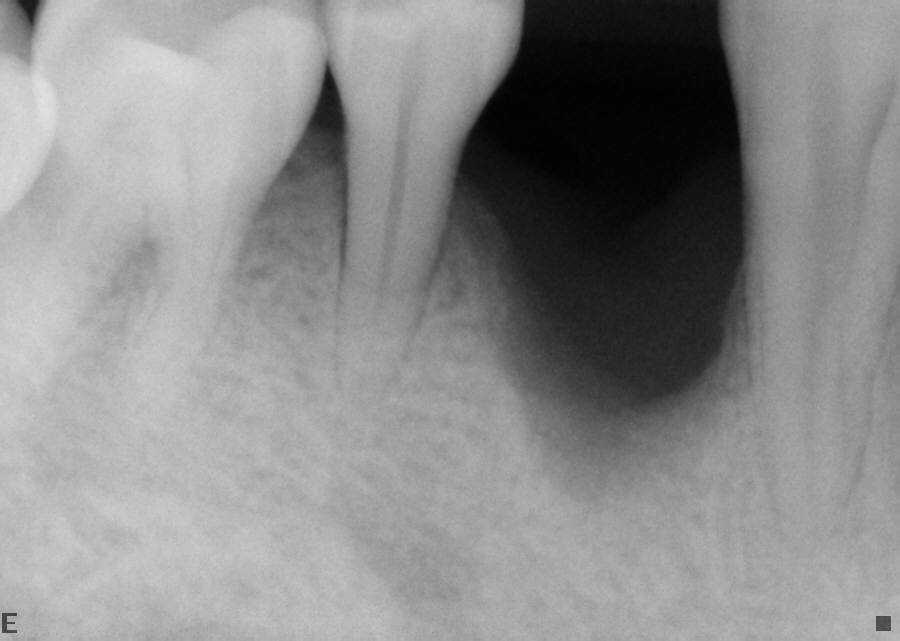

Orthodontic Treatment X-ray - Before

After Series of Teeth Extractions, Upper Left Canine Unerupted.

Ready to Start Ortho Treatment